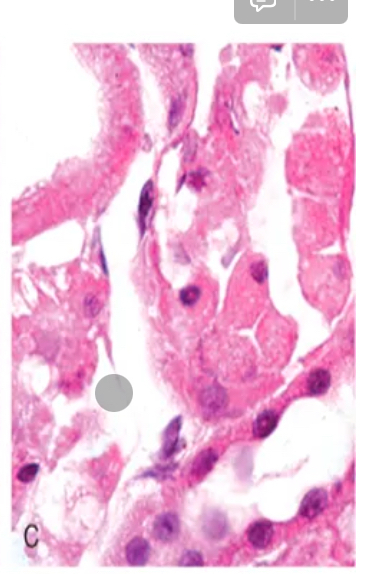

como se ve la necrosis grasa macro y micro?

Micro: rosa, cels amorfas, sin núcleo.